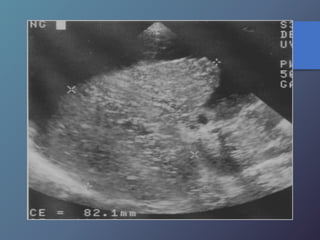

Mt Hiperecoicas

• Ecográficamente se presentan las lesiones

de tamaño variable con presencia de un

halo hipoecoico.

• Diferenciar lesiones malignas de benignas

por presencia de halo hipoecoico.

• Se describen como lesiones ecógenas,

hipoecoicas, en diana, calcificadas,

quísticas y difusas.